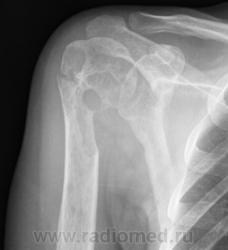

Какая патология по Вашему мнению, коллеги, на снимках?

1. В обоих случаях - мета-эпифиз (а там, даже у взрослых - крастный костный мозг).

2. Полостные структуры.

3. В первом и во втором случаях - дефекты кортикального слоя с остеопоротической компонентой. На левом снимке и полее мелкие полостные образования.

Я на 1 место поставлю любимый мною "тубер", на второе - "мета"

Еще версии? обратите внимание на скиалогию очагов! Ничего не напоминает?

Ну, не ГКО-же?

На мой взгляд, здесь озлакочествленное что-то первично доброкачественное (во загнул).

А почему нет?